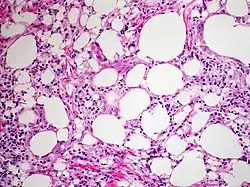

At the microscopic scale, lipoid pneumonia is characterized by abundant foamy macrophages and giant cells. There may also be lipoid vacuoles, and cholesterol clefts.[3] If necrosis is present, there is likely an infection such as secondary tuberculosis.[3]